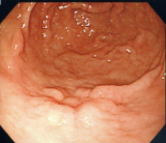

早期胃がんのESD症例

早期のがんを内視鏡と特殊なナイフを使用して切り取る方法をご紹介します。

1. がん病変を確認 |